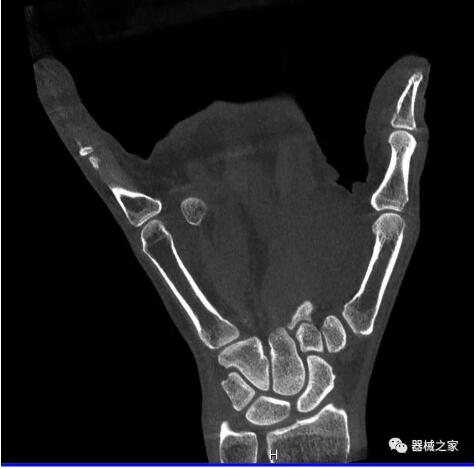

以下是這些“特立獨(dú)行”的CT所拍出來的圖像: